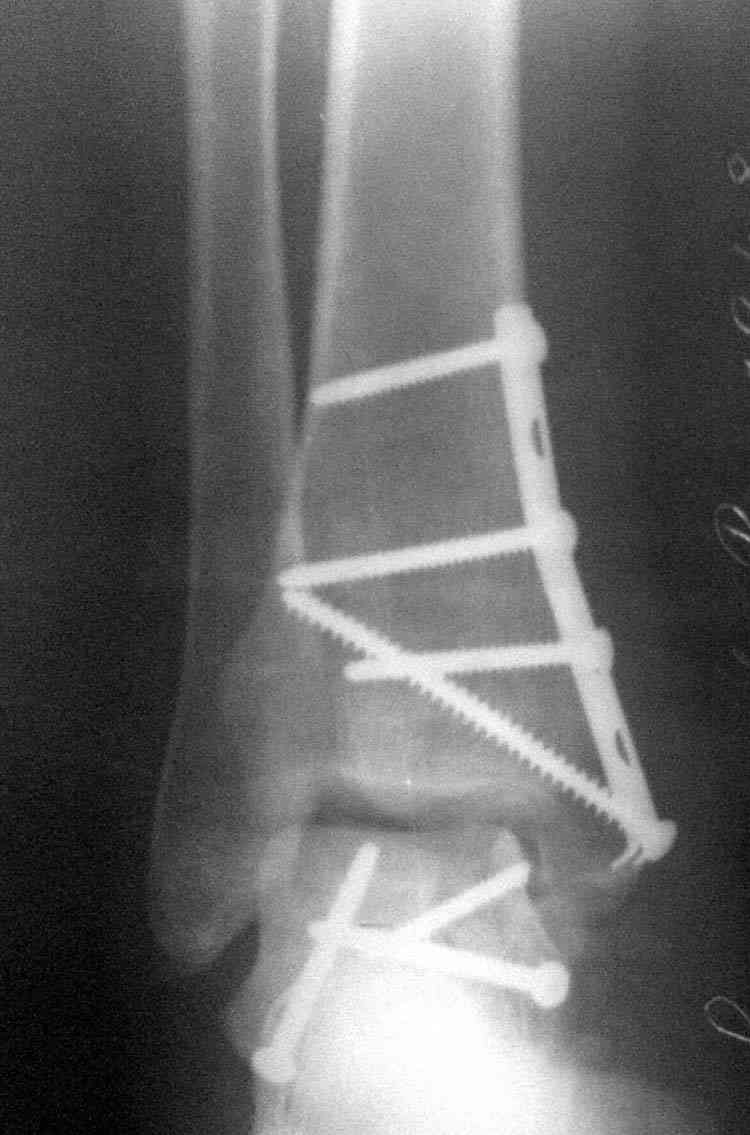

И второй случай из недавней ташкентской практики, (извините за качество ренгенограммы и только в одной проекции) случай падения с высоты (кстати моего друга - известного киноактера) - открытый

смещенный перелом тарана, с переломом переднего края дистального эпиметафиза большеберцовой кости.

При поступлении в приемной сделана первичная обработка с ушиванием открытой латеральной раны и вытяжением за пятку.

Из-за отсутствия времени пришлось оперировать на второе утро, из материала, что имеем на месте, фиксирован двумя шурупами, а третий-это контур сломанного жойстика в 4 мм. На дистальный медиальный конец тибиа antiglide 3.5 мм пластина. Через пару дней выписан и несмотря на предупреждение, самостоятельно начал нагрузку в 4 недели, время не ждет, снимается в боевике в Росийской Федерации.